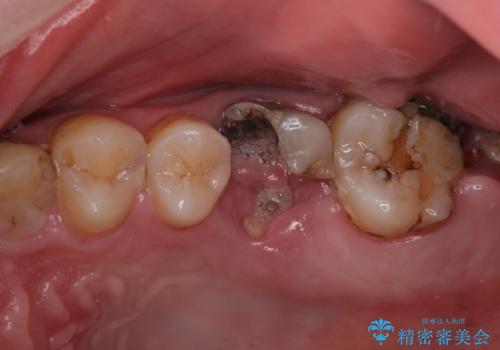

- 口の中をマスク生活の間に全て治したい、見た目を良くしたいとの事で来院。

まず徹底的に虫歯を取り除き、保存が出来ない部位は抜歯(親知らずを含む)を行い、根管治療が必要な部位は精密根管治療を行いました。

その後、インプラント治療、セラミック治療を行いました。

一度治療するはを全て仮歯に変えて、歯茎を整えてからセラミックを装着しました。

また、虫歯が歯肉の中まである場合はAPF(歯肉弁根尖側移動術)も行なっています。